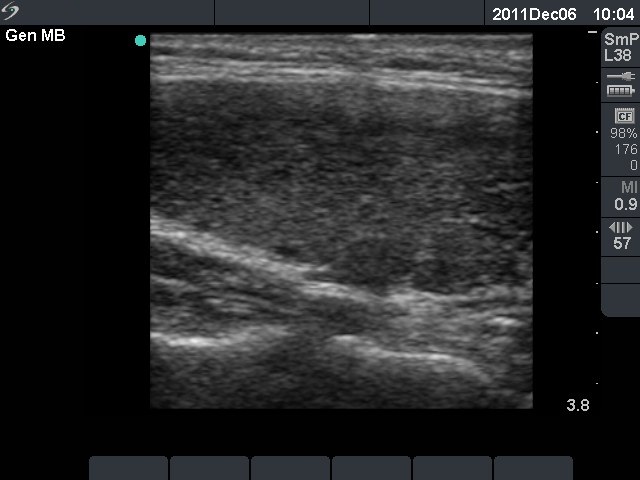

Second examination 3 months later (3rd row of images)

Clinical presentation: the complaints of the patient had decreased.

Palpation: no abnormality.

Functional state: euthyroidism with TSH-level 3.60 mIU/L, FT4 13.1 pM/L.

Ultrasonography: the degree of hypoechogenicity and the previously increased vascularization have decreased, as did the size of the thyroid.

We suggested follow-up examination with yearly TSH determination, in the case of pregnancy at once.